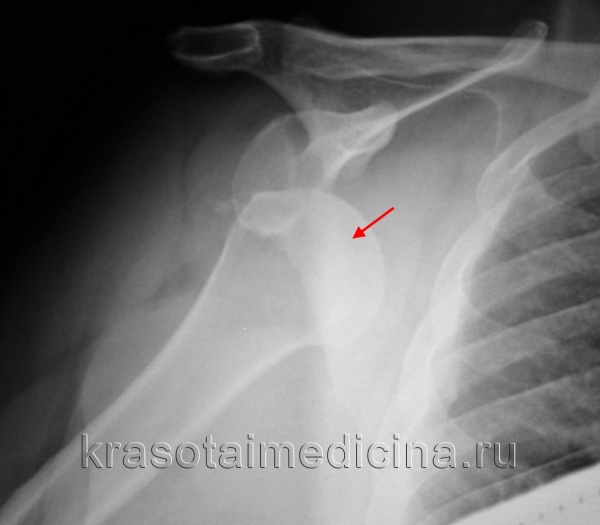

Рентгенография при вывихе плеча

Для уточнения диагноза вывиха плеча и выявления сопутствующих повреждений плечевой кости и лопатки проводится рентгенологическое исследование в двух проекциях. В случаях застарелого вывиха плеча может потребоваться МРТ плечевого сустава.

Рентгенография плечевого сустава: вывих головки правой плечевой кости из суставной ямки.